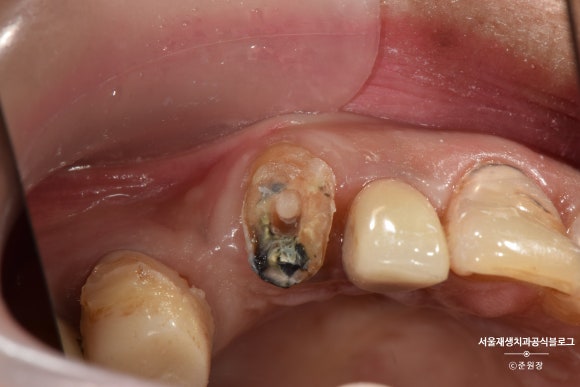

깊은 충치로 머리가 간신히 남은 치아입니다.

머리도 얼마 안남았는데...

크라운을 씌우기 불안할 만큼 잔존치질이 부족합니다.

이 경우 가장 흔하게 선택하는 정답지는,

발치 후 임플란트겠지요.